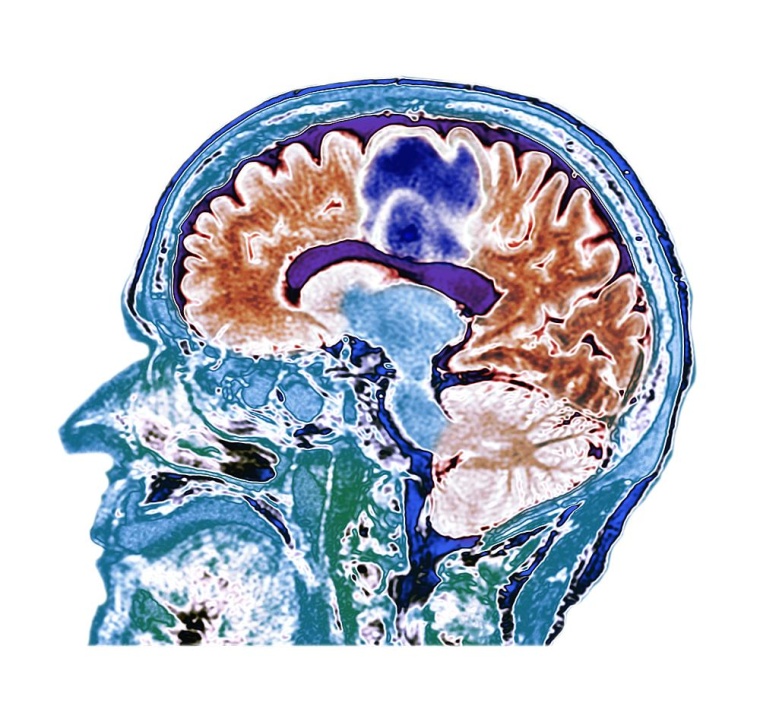

Das Forschungsprojekt unter Leitung der TU-Forschenden Sara Ellenrieder und Professor Peter Buxmann untersuchte die Nutzung von ML-basierten Entscheidungsunterstützungssystemen in der Radiologie, speziell bei der manuellen Segmentierung von Hirntumoren in MRT-Bildern. Im Fokus stand die Frage, wie Radiolog*innen von diesen Systemen lernen können, um ihre Leistungen und Entscheidungssicherheit zu verbessern. Die Autor*innen verglichen dabei unterschiedlich leistungsfähige ML-Systeme und analysierten, wie die Erklärung des ML-Outputs die Nachvollziehbarkeit der Ergebnisse für die Radiolog*innen verbesserte. Das Forschungsziel ist es, herauszufinden, wie Radiolog*innen langfristig von diesen Systemen profitieren und diese sicher einsetzen können.

Dazu führte das Projektteam ein Experiment mit Radiolog*innen verschiedener Kliniken durch. Die Mediziner*innen wurden gebeten, Tumore in MRT-Bildern zu segmentieren, bevor und nachdem sie ML-basierte Entscheidungsunterstützung erhalten hatten. Dabei wurden verschiedenen Gruppen unterschiedlich leistungsfähige oder transparente ML-Systeme an die Seite gestellt. Neben der Erfassung quantitativer Leistungsdaten während des Experiments sammelten die Forschenden auch qualitative Daten mittels „Think-Aloud“-Protokollen und anschließenden Interviews.

Im Rahmen des Experiments wurden 690 manuelle Segmentierungen von Hirntumoren durch die Radiolog*innen vorgenommen. Die Ergebnisse zeigen, dass Radiolog*innen von den Informationen lernen können, die leistungsstarke ML-Systeme bereitstellen. Durch die Interaktion verbesserten sie ihre Leistung. Allerdings zeigt die Studie auch, dass fehlende Erklärbarkeit von ML-Output bei leistungsschwachen Systemen durchaus zu einem Leistungseinbruch bei den Ärztinnen und Ärzten führen kann. Besonders interessant ist, dass die Bereitstellung von Erklärungen des ML-Outputs nicht nur die Lernerfolge der Radiolog*innen verbesserte, sondern auch das Lernen fehlerhafter Informationen verhinderte. Tatsächlich konnten einige Mediziner*innen sogar aus Fehlern lernen, die leistungsschwache, aber ihren Output gut erklärende Systeme machten.